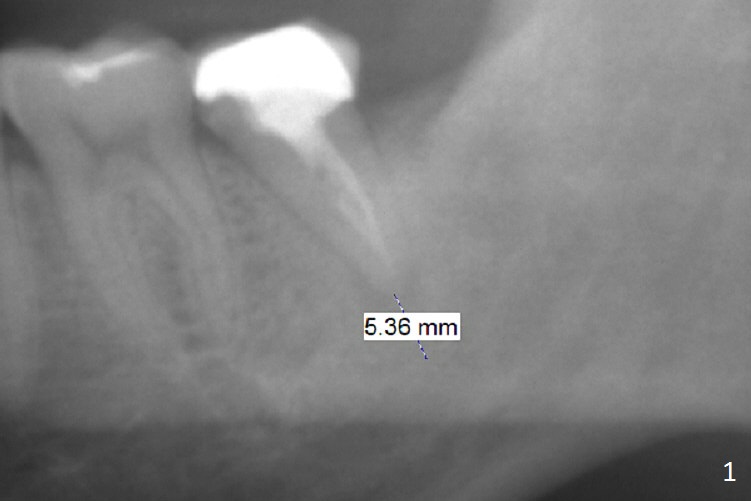

A 45-year-old man has had trouble with the tooth #18 for long time. First, the tooth needed RCT and crown retreatment several years ago (Fig.1). Now there is 2nd caries underneath the crown (Fig.2). After extraction and No Antibiotic, an IBS or Tatum implant will be placed (Fig.3).